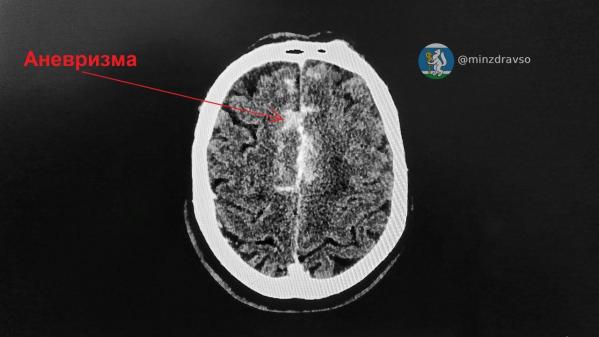

Медики доставили мужчину в состоянии комы в ГКБ №14. Специалисты провели обследования и выявили аневризму передней соединительной артерии и массивное кровоизлияние. Чтобы спасти пациента, решено было сделать ему срочную операцию в Региональном сосудистом центре на базе ГКБ №40, куда пациента экстренно доставили.